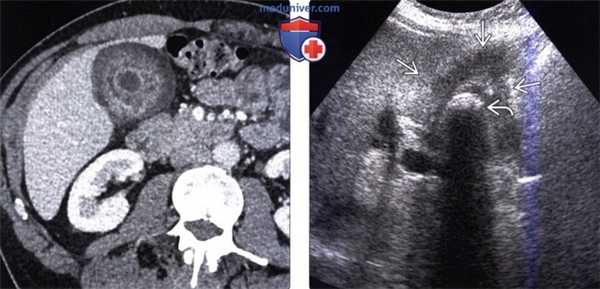

(Левый) У пациентки 67 лет с острым панкреатитом на сагиттальном УЗ срезе определяется крупное полипоидное объемное образование дна желчного пузыря, имеющее собственную сосудистую сеть.

(Правый) При МРТ в просвете желчного пузыря визуализируется дольчатое полипоидное образование, гетерогенное и гиперинтенсивное по сравнению с прилегающей печенью. Обратите внимание на угловатый конкремент в шейке желчного пузыря и отечность поджелудочной железы, вызванную острым интерстициальным отечным панкреатитом.

(Левый) У женщины 37 лет с острыми болями в правом верхнем квадранте живота на сагиттальном УЗ срезе желчного пузыря визуализируются отбрасывающие тень конкременты и сладж, а также опухолевидное дольчатое локальное утолщение стенки, прорастающее трансмурально.

(Правый) При КТ с контрастным усилением в режиме мульти планарной реконструкции в той же сагиттальной плоскости определяется полипоидное объемное образование стенки желчного пузыря, накапливающее контраст.